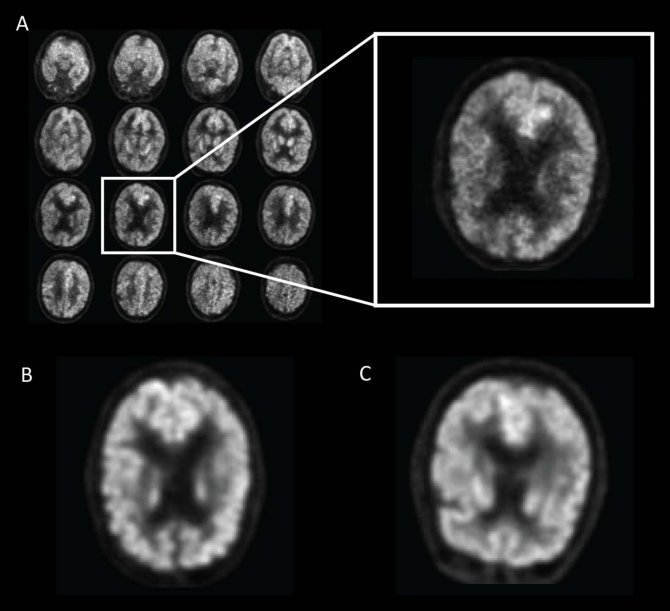

Imágenes cerebrales obtenidas a partir de escaneos con una técnica especial de tomografía por emisión de positrones. La imagen A corresponde a un hombre de 76 años con Mal de Alzheimer. La B, a una mujer de 83 años con deterioro cognitivo leve. La C, a un hombre de 80 años sin Mal de Alzheimer ni deterioro cognitivo leve. El paciente con Mal de Alzheimer tenía en su cerebro un poco menos de materia gris que el paciente sin Mal de Alzheimer ni deterioro cognitivo leve. La diferencia entre la paciente con deterioro cognitivo leve y el que no tenía Mal de Alzheimer ni deterioro cognitivo leve resultaba prácticamente imperceptible a simple vista. (Imágenes: Radiological Society of North America)